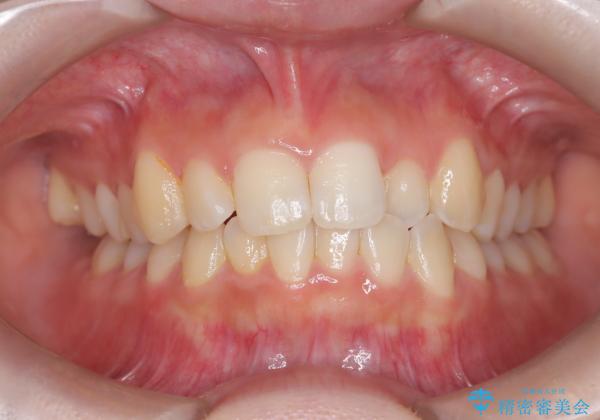

- 右上の前歯(2番)が下の歯より内側に入っている反対咬合を主訴にご来院されました。精密な検査の結果、この反対咬合を解消するためには、右上の歯列に前歯を出すためのスペースを確保する必要があると判明しました。患者様のご希望に合わせ、透明で目立たないインビザライン(マウスピース矯正)による治療計画を立案。奥歯全体を奥へ動かす遠心移動でスペースを作り、反対咬合を解消することを目指します。

今回の矯正治療では、透明なマウスピース型の装置インビザラインを使用しました。治療は、緻密なデジタル計画に基づき、奥歯から順に歯列全体を後方へ移動させる遠心移動を実施し、前歯を前に出すためのスペースを確保しました。このスペースを利用して、内側に入り込んでいた右上2番をスムーズに前方に誘導し、正常な咬み合わせへと改善。目立たないインビザラインで、機能的な咬み合わせと美しい前歯の並びを獲得していただけました。